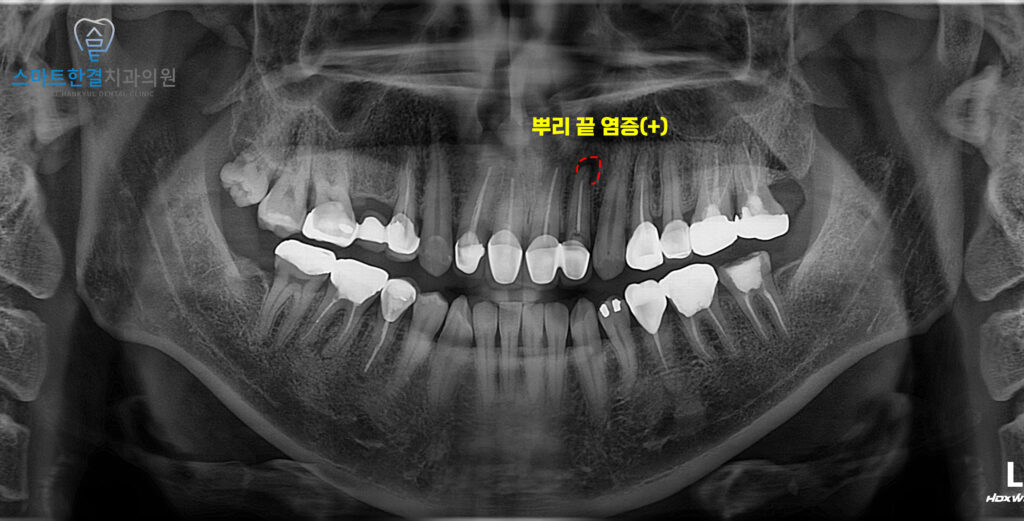

파노라마 사진을 확인해 보니,

왼쪽 위 앞니에 뿌리 끝으로 염증이

잡혀있는것을 확인할 수 있었어요.

기존 신경치료가 시간이 지나면서

완전하게 처리되지 않았거나,

근관 내부에 미세한 세균이

남아 있었던 것으로 보여요.

이로 인해 염증이 계속해서 진행되어

잇몸에 고름이 차는 증상이 나타났으며,

통증이 동반되면서

불편함을 초래하게 되었어요.